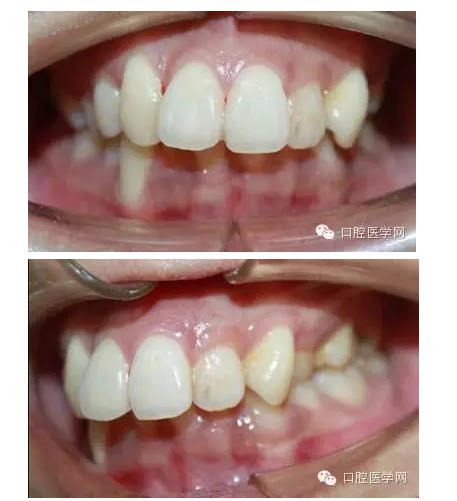

這是一位我同事接診的一位患者,成年女性,安氏II類,高角,下頜后縮,重度深覆合,上下中線右偏,原本做過(guò)一次矯正,4個(gè)4已經(jīng)拔除。

這個(gè)患者,II類高角,下頜后縮,所以我們不能抬高磨牙,另外兩個(gè)上頜中切牙牙根短小,也不能大幅壓入。